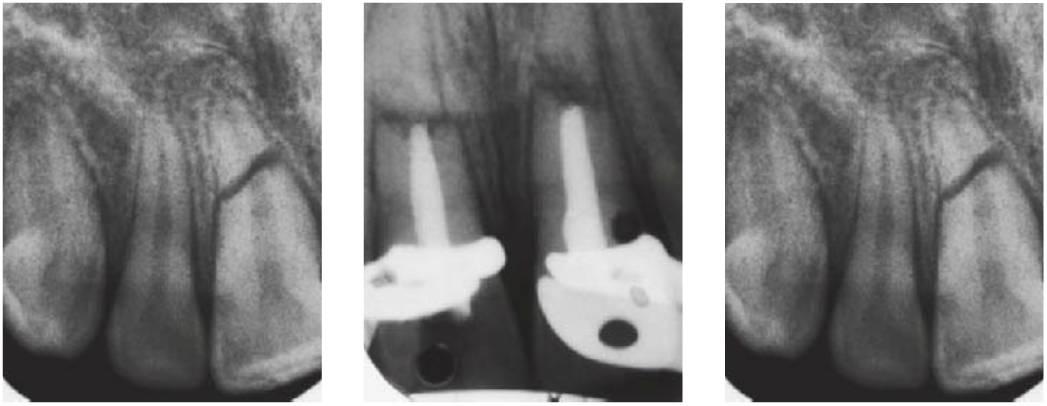

Luxación lateral y extrusiva

Los dientes pueden luxarse en cualquier dirección, y pueden recolocarse y ferulizarse en función de la extensión de la luxación. Ambas acciones pueden realizarse mediante presión digital o con fórceps. En caso de utilizar fórceps, se debe cuidar de no dañar la superficie de la raíz y sujetar el diente sólo por la corona. Los dientes estarán visiblemente desplazados, potencialmente móviles y presentarán cambios radiográficos en el ligamento periodontal. Inicialmente, las pruebas de sensibilidad pulpar podrían dar resultados negativos.

Tratamiento

- Reposicionamiento con anestesia local. Se debe realizar en las primeras horas (fig. 7.27A, B) ya que suele resultar extremadamente difícil movilizar el diente cuando el paciente se presenta 24 horas después.

- Suturar laceraciones gingivales.

- Fertilización flexible con resina composite y alambre (fig. 7.24C, D) o aparatología ortodóncica durante 2 semanas para la luxación extrusiva y durante 4 semanas para la luxación lateral debido a la fractura de hueso alveolar concomitante.

- Antibióticos, profilaxis tetánica y enjuague bucal con gluconato de dorhexidina al 0,2%, si fueran necesarios.

Las luxaciones laterales cuentan siempre con un componente de fractura dentoalveolar, y resulta importante moldear y recolocar el hueso en la posición correcta conservando siempre los fragmentos de hueso que se encuentran unidos al periostio.

Revisión

- Revisión cada 2 semanas mientras la férula esté en su sitio; posteriormente, a los 1, 3, 6 y 12 meses hasta 5 años.

- Prueba de sensibilidad pulpar.

- Radiografías en cada visita.

Pronóstico

- Depende del grado de desplazamiento y de desarrollo del ápice. La cicatrización es excelente en dientes inmaduros.

- Se presenta necrosis pulpar en el 15-85% de los casos, y es más prevalente en dientes con ápices cerrados.

- La obliteración del conducto pulpar se produce con frecuencia en dientes con ápices inmaduros.

- La reabsorción es infrecuente.

- La destrucción apical transitoria (2-12%) es una expansión del espacio apical del ligamento periodontal. No está indicado comenzar con un tratamiento de conductos radiculares a menos que haya otros indicadores de infección del conducto pulpar.

Fracturas dentoalveolares

Al luxarse los dientes, puede fracturarse o deformarse la tabla alveolar. Utilícese la presión firme de un dedo sobre las tablas bucal y lingual para el reposicionamiento. Debe recordar se que las fracturas alveolares pueden producirse sin implicación dental de consideración. Estas fracturas deben ferulizarse durante 4 semanas en niños y de 6-8 semanas en adultos. Por lo general, los dientes luxados o avulsionados ocasionan fractura y/o desplazamiento del hueso alveolar, y por ello se debe ejercer una firme presión para realinear los fragmentos óseos. La ferulización puede ser rígida o semirrígida y depende del grado de lesión y del número de dientes implicados.